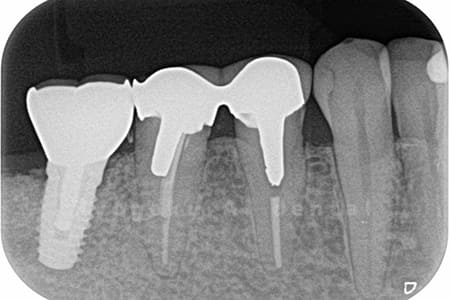

- 縁下カリエス、慢性根尖性歯周炎、不良補綴

- クラウンレングスニング、マイクロエンド、フルジルコニアクラウン

虫歯が神経まで及ぶと共に、歯茎の中まで虫歯が及んでいました。根の治療(マイクロエンド・根管治療)を行なった後、クラウンレングスニング・歯周外科を行い、ジルコニアの被せ物を行った患者様です。